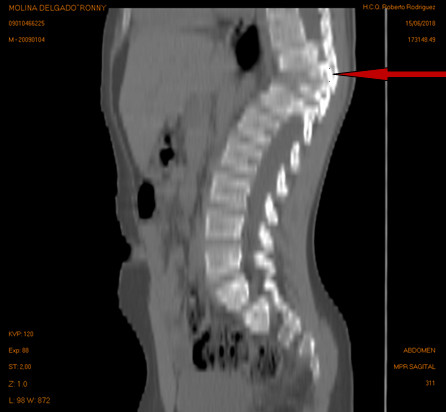

Volver a los detalles del artículo Tuberculosis vertebral